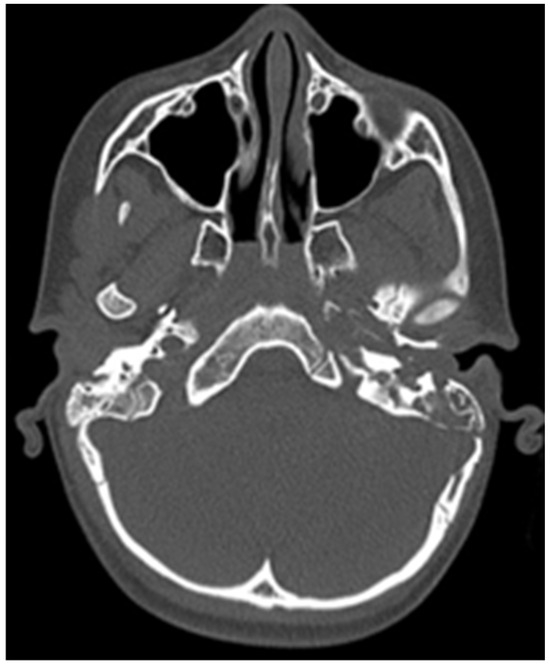

CT of the head was performed, which showed destruction of the left mastoid process from a soft tissue tumour mass, which involves the cavities of the middle ear, tympanic cavity and the external auditory channel (Figure 2 and Figure 3).

Figure 2. Initial CT of the patient.

Figure 3. Initial CT of the patient.

After these CT findings, an examination by an ENT specialist was performed—left external auditory canal was completely obstructed by a soft tissue formation, which resembles granulation tissue, left tympanic membrane was impossible for observation. Second diagnosis was established—peripheral facial nerve palsy, caused by middle ear chronic inflammation. So the patient was transferred to an ENT clinic for surgical treatment.